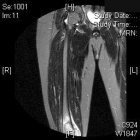

J.S. - 12 year old boy c/o right knee pain and swelling for ten days. Painful at rest, worse at night and with activity. Able to ambulate with pain. Initially the pain was accompanied by fever, chills, malaise, nausea and vomiting; all of which have resolved.

Zoom image: Radiological image Radiological image.

Zoom image: Radiological image